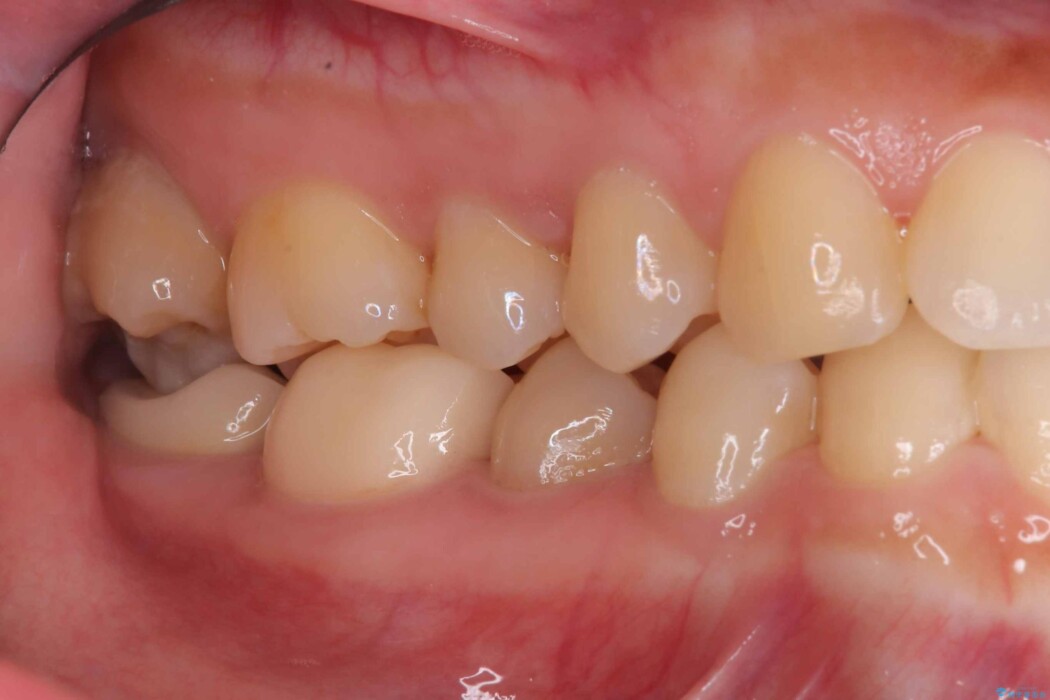

除去後は、再発リスクを抑え長期的な安定を図るために、適合精度が高く劣化しにくいセラミックインレーによる修復を計画しました。